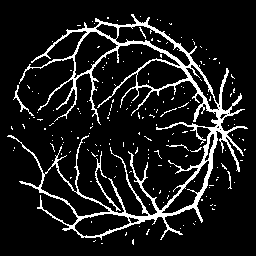

The following provides quantitative comparisons of three FCNs respectively. Example results on various image-to-image mapping tasks are shown in Figure 2.

Figure 2: Example results of three FCNs (from left to right: input, ground truth, the output of FCN-16s, U-Net and our model) on various tasks (from top to bottom: EM segmentation, vessel extraction and raindrop removal)